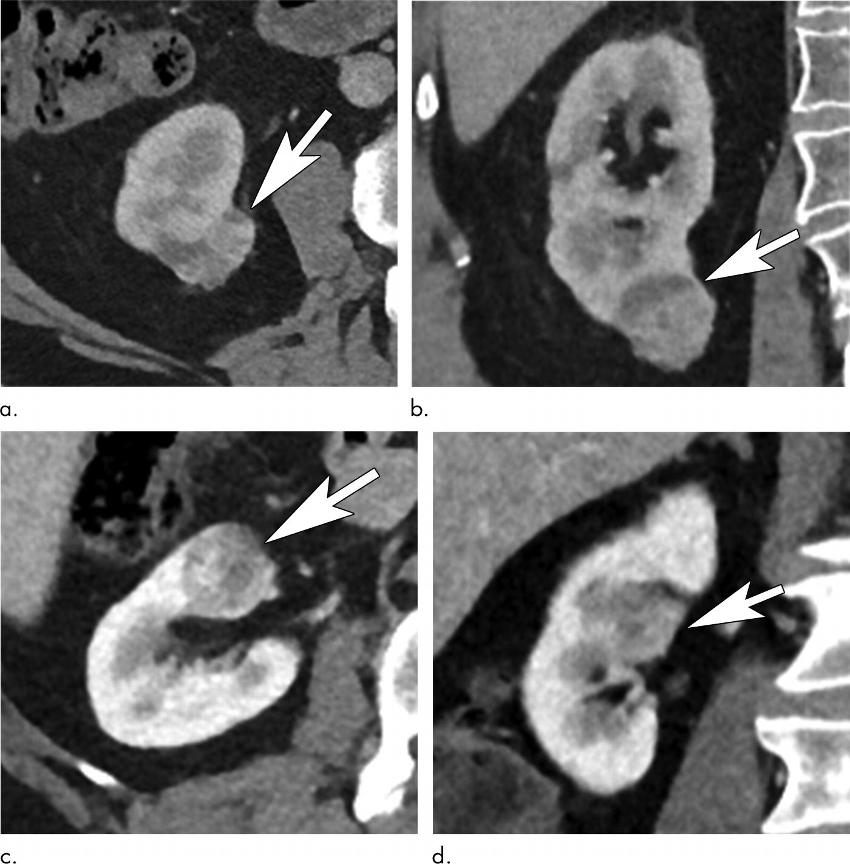

Figure 4. Renal tumors show low and high anatomic complexity. Contrast-enhanced (a) axial and (b) coronal abdominal CT images in a 70-year-old man diagnosed with a right renal tumor (arrows) Nephrometry score of 4 indicated noncomplex tumor anatomy. In the setting of mild (stage 2) chronic kidney disease, the Renal Anatomy and Function for Indeterminate Renal Mass model results would favor partial nephrectomy. Axial (c) and coronal (d) CT images in a 70-year-old man diagnosed with a centrally located renal neoplasm (arrows). The nephrometry score of 10 indicated high anatomic complexity because of interpolar location and contact with the collecting system and renal hilar vessels.